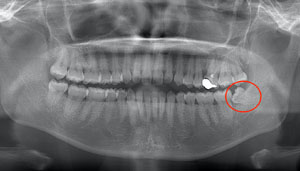

右下奥歯が痛い症例

- 抜歯前写真(レントゲン)

- 抜去歯の写真(CT画像)

| 年齢 | 40代・男性 |

|---|---|

| 主訴 | 右下奥歯が痛い |

| 親知らずの生え方 | 斜めに生えている |

| 抜歯時間 | 30分 |

| 費用 | 約6,000円(保険診療、CT代含む) |

| 抜歯内容 | レントゲン上で右下の親知らずが大きく虫歯になっており、斜めに生えていることもあり患者様の希望により抜歯することとなりました。 当日は痛みがあったため抗生剤と鎮痛剤にて炎症を抑え、後日歯ぐきを切開し、抜歯を行いました。 レントゲン上でも分かるように親知らずの根が二つに分かれており根が折れてしまう可能性がありましたが、このケースでは事前にCTを撮影し、歯の位置、根の方向を確認していたため根が折れることなく抜歯ができました。 術後数日は腫れと痛みがありましたが、薬の服用で抑えることができ、1週間後の糸取りの際には痛み、腫れともになくなっていました。 |